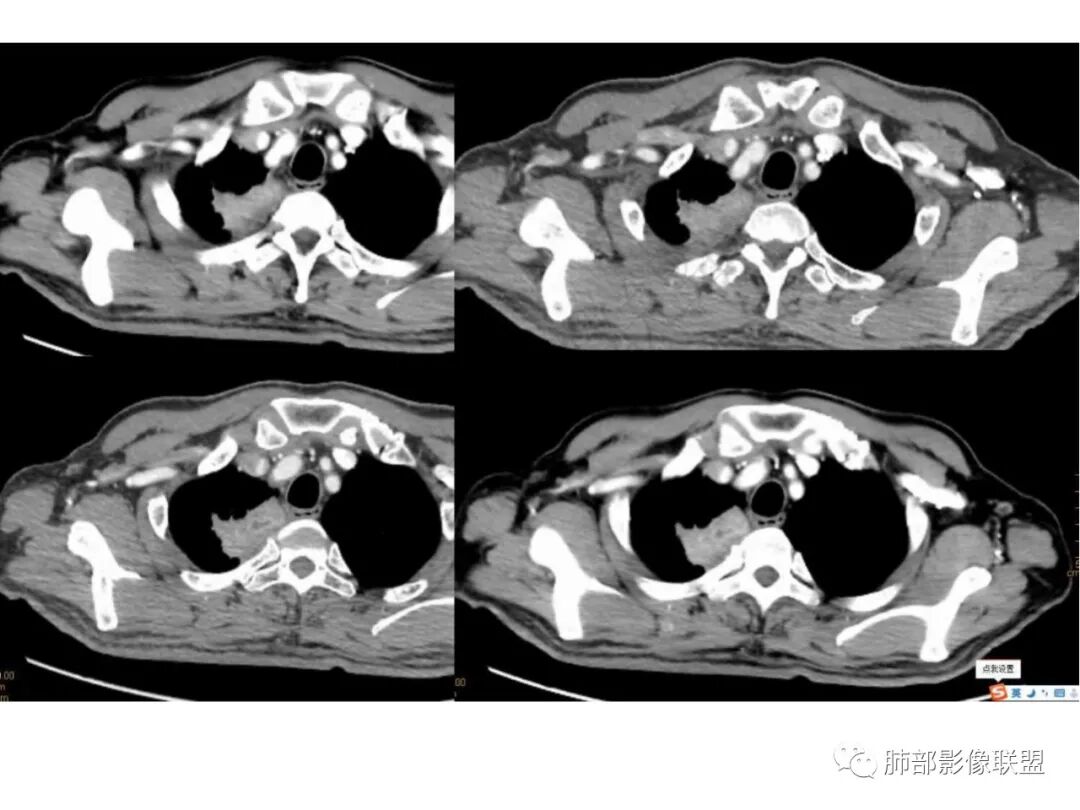

右上叶尖段带状实变影

外围大、内带小,宽基底与胸膜相连,附近卫星灶

支气管进入病灶内,广泛胸膜增厚

支气管粘液栓

血管走形自然

边缘平直为主

支气管堵了,但是远端粘液栓:是粘液栓堵塞?还是狭窄或堵塞后继发粘液栓?

病灶是支气管腔内堵塞导致远端实变、不张?还是外围病灶融合、实变影响近端支气管?

整体考虑肿块应该不支持,因为支气管、血管走形还算自然,只是收缩在一起,如果肿块走形不会这么自然,会推移、变形,侵犯

现有的图显示近端支气管还是连续的,只是远端扩张,腔内粘液栓,其实还应当看重建的支气管连续的图,与近端含气部分的连续